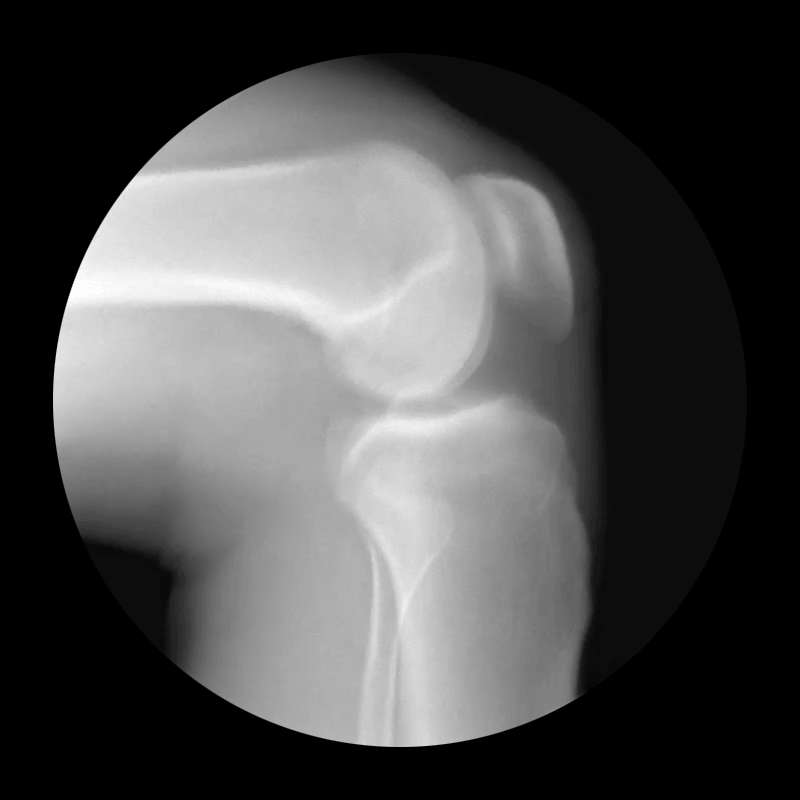

Knee

While they look like something between a trailer for a new horror movie and a lesson from a college anatomy class, there's something very mesmirizing about the perfectly looped X-rays. Oh, and as a person who has dislocated his kneecap several times, that knee GIF is particularly painful to watch.